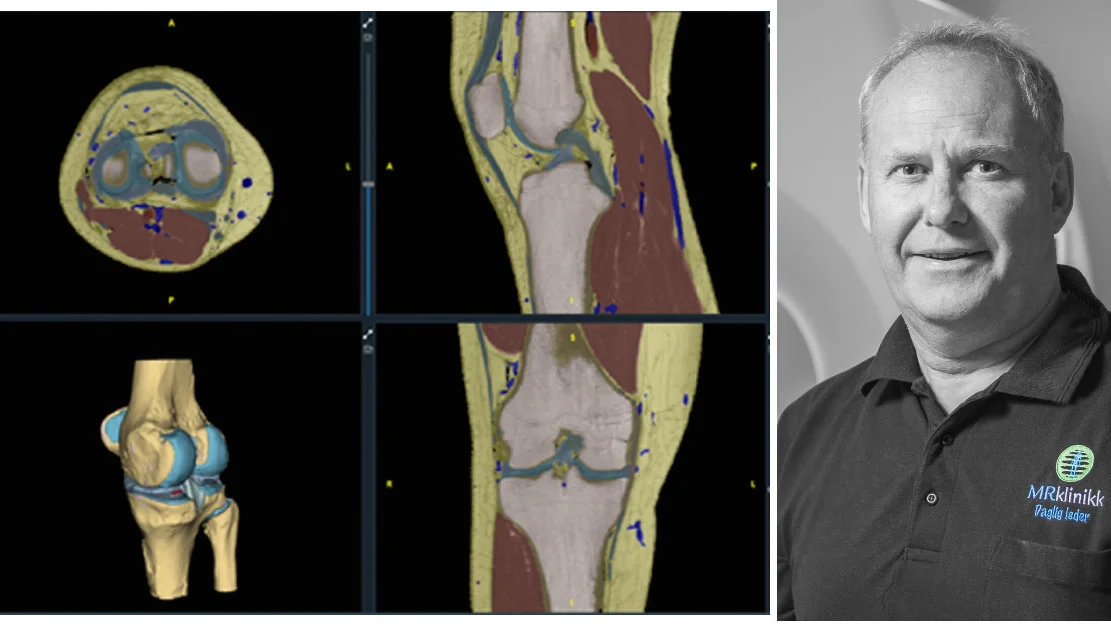

– Bare å stå på ei sånn liste er helt fabelaktig for oss, og det betyr ingenting om vi ikke vinner eller går videre, forteller gründer Kjell-Inge Gjesdal til NETT NO.

Nordiccad er sprunget ut av Sunnmøre MR-klinikk på Moa, som Gjesdal har drevet siden 2003. Han forteller at de hele tiden har drevet med forskning ved siden av å være et institutt innen radiologi. Blant annet har Gjesdal og samarbeidspartnerne fulgt utviklingen innen kunstig intelligens tett.

– Vi er tidlig ute med å produsere medisinsk retta programvare i Norge som baserer seg på bruk av kunstig intelligens. Så vidt vi vet, er det ingen andre i Norge som gjør dette, forteller han.

Den nominerte programvaren går under navnet «MRI Segmentation Tool – som forkortes MST. Nordiccad og Sunnmøre MR-klinikk har samarbeidet med NTNU og Helse Møre og Romsdal om utviklingen.